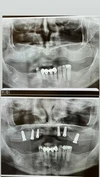

Implant Treatment